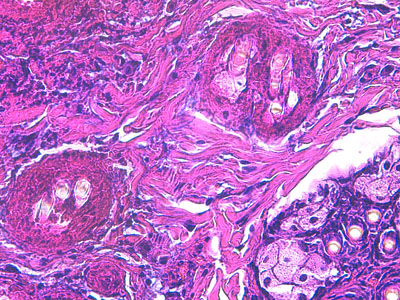

- l’examen histopathologique de deux biopsies cutanées (Photos 12 et 13) confirme l’existence d’une sévère dermatite nécrosante et ulcérative, avec lésions secondaires de pyodermite profonde, associées à une nécrose des annexes pilo-glandulaires. En dépit de l’absence de corps d’inclusion viraux nettement objectivables en position intra-nucléaire, l’aspect histopathologique est fortement évocateur d’une virose cutanée.

Photo 13 : Examen histopathologique de biopsies cutanées (LAPVSO)